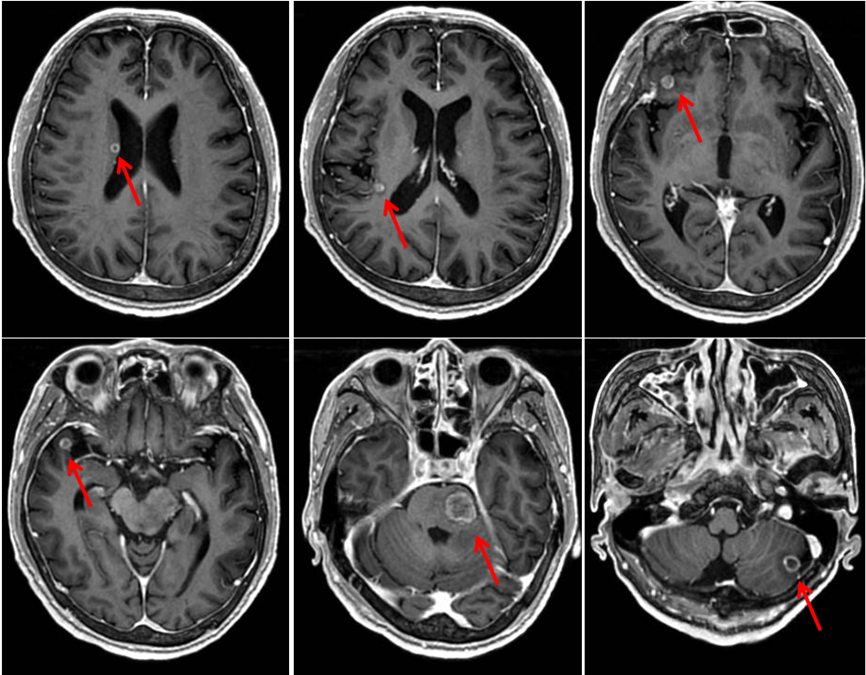

完善顱腦強化MRI檢查示:腦干、左側小腦半球、右側額顳葉、右側基底節放射冠區多發占位性病變,符合轉移瘤表現(圖2)。

圖2.腦干、左側小腦半球、右側額顳葉、右側基底節放射冠區多發占位性病變。